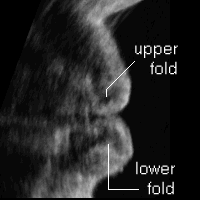

4D lips - a side view

Functional 2D images reformatted from the same 4D data (upper [GIF 135 KB]). See how the tiny muscles in your lips (two sets of the folding deeper & superficial orbicularis oris) straighten out when you pout.